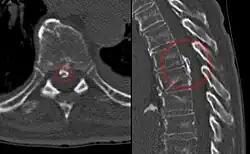

CT scan of the spine, showing calcification of the longitudinal posterior ligament